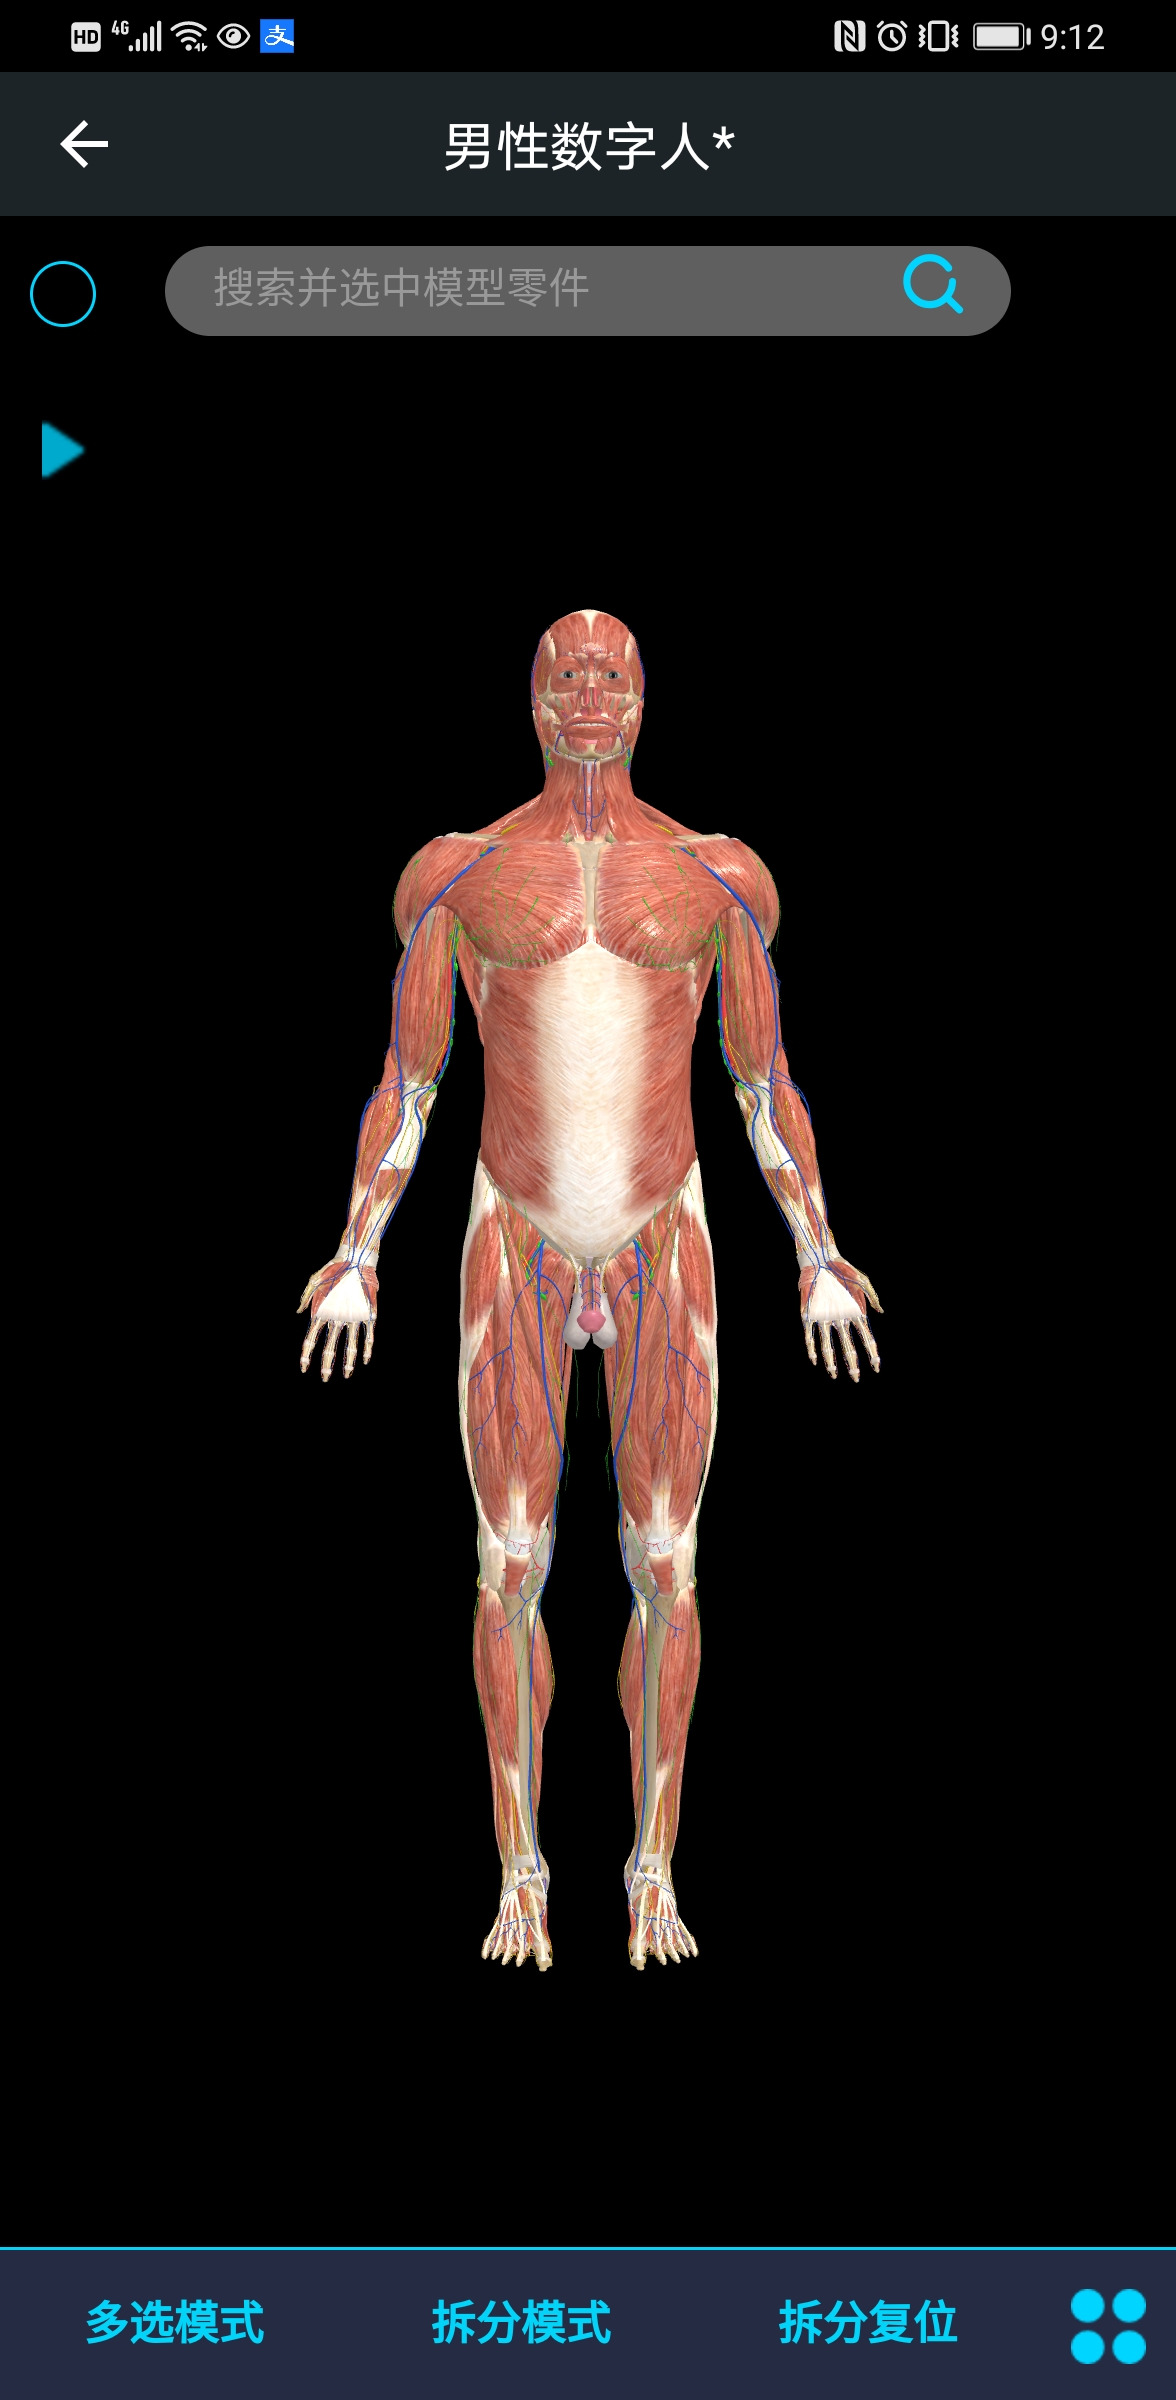

医维度人体解剖软件是一款专为医学教育和临床学习设计的高精度三维人体解剖软件,它提供了详尽的人体结构展示和互动学习功能,帮助用户深入理解人体解剖知识。

该软件结合了最新的三维建模技术和医学影像学数据,确保所有解剖结构的高精度还原,为用户提供逼真的学习体验。

许多用户称赞该软件的三维模型精细度高,能够清晰地展示人体各个部位的细节结构,有助于深入理解解剖知识。

软件内置的互动学习功能,如旋转、缩放、标注等,让用户能够自由探索人体结构,增强了学习的互动性和趣味性。